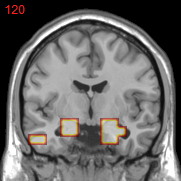

Figure 2: Feature selection by different models. The top row illustrates selected voxels in a 3D model (voxels with positive β𝛽\beta are in brown and negative ones are in blue), the mid and bottom rows illustrate the corresponding projections on brain slices.

Feature selection. For each task, the selected features are those whose β𝛽\beta are not zero . In Figure 2, the result of 30ADNC is used to illustrate the feature selection by different models (using the parameters at their best accuracy). As shown, the selected voxels by both GFL and n2superscript𝑛2n^{2}GFL cluster into several spatially connected regions, whereas those of lasso and T-test/MLDA scatter around. Also, as mentioned before, the LapL tends to select much more voxels than necessary due to the l2subscript𝑙2l_{2} regularization. Moreover, the selected voxels by GFL and n2superscript𝑛2n^{2}GFL are concentrated in Hippocampus, ParaHippocampal gyrus (which are believed to be the early damaged regions). On the other hand, the lasso and T-test/MLDA either select less lesion voxels or select probably noisy voxels not in the early damaged regions.